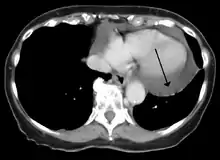

Cardiac CT and MRI scans: cross-sectional imaging with computed tomography (CT) can help localize and quantify the effusion, especially in a loculated effusion (a effusion contained to one area).[11] CT imaging also helps assess for pericardial pathology (pericardial thickening, constrictive pericarditis, malignancy-associated pericarditis).[1] Whereas cardiac MRI is reserved for patients with poor echocardiogram findings and for assessing pericardial inflammation, especially for patients with continued inflammation despite treatment.[4] CT and MRI imaging can also be used for continued follow up on patients.

A CT scan showing a pericardial effusion